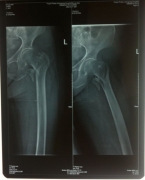

7月9日,莆田盛興醫(yī)院為一名89歲的女性髖部骨折患者順利實(shí)施了手術(shù)。   數(shù)日前,東……

近日,平海鎮(zhèn)90歲高齡的周阿婆即將出院。她感慨地對(duì)筆者說(shuō):“真沒想到我還能下床走路……